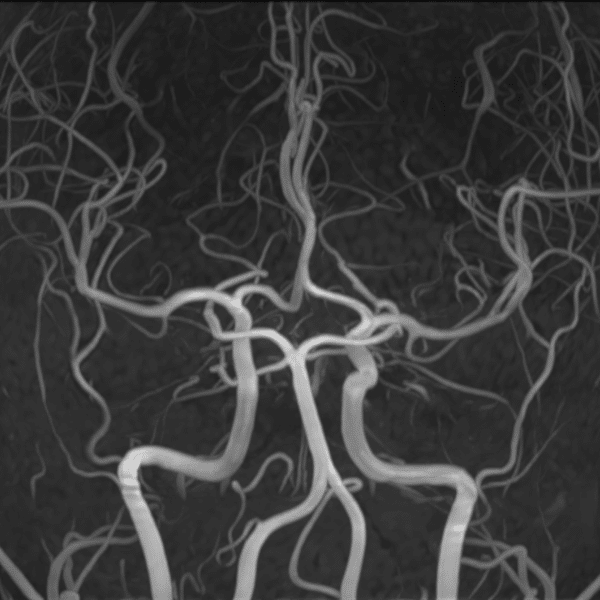

Brain MRA

3.0T Siemens MAGNETOM Skyra

3D TOF

(L) 0.5×0.6×1.2 mm,

(R) 0.5×1.0x1.2 mm, MIP

Conventional SwiftMR™ 07:12 03:13 (68% Faster)